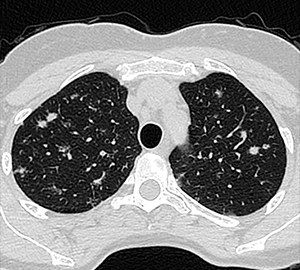

Masculino 75 años, APP: TBC, MC: Tos productiva crónica y disnea.